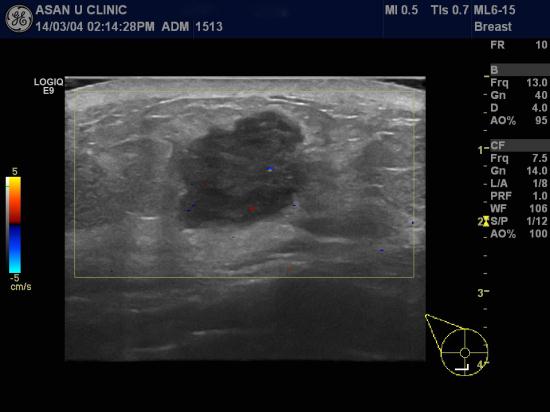

어느날 갑자기 우측 유방 아래부분에 멍울이 만져져 내원하신

47세 미혼 여성 분입니다.

마지막 검사력은 5,6년전 유방촬영이였다고 하시네요.

유방초음파상 이상소견 보인 6시반방향과 9시방향에서

각각 유방의 침윤성 유관암이 조직검사로 확인되었으며,

같은쪽 겨드랑이에 비대된 림프절에서도 전이암이 진단되어

현재 정밀 검사중입니다.